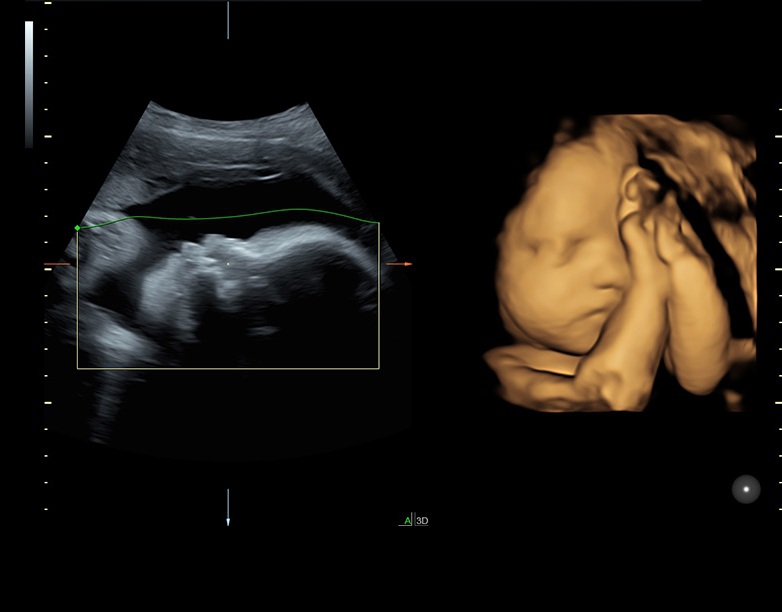

• Технология SonoRenderlive: Эта технология облегчает получение 3D/4D изображений путем автоматического изменения положения плоскости визуализации в зависимости от движений плода. Она позволяет получить реалистичные и объемные изображения, что полезно для демонстрации плода будущим родителям и для дополнительного анализа.

• HDlive в 3D и 4D - режим перемещаемого виртуального источника освещения - "виртуальная фетоскопия"